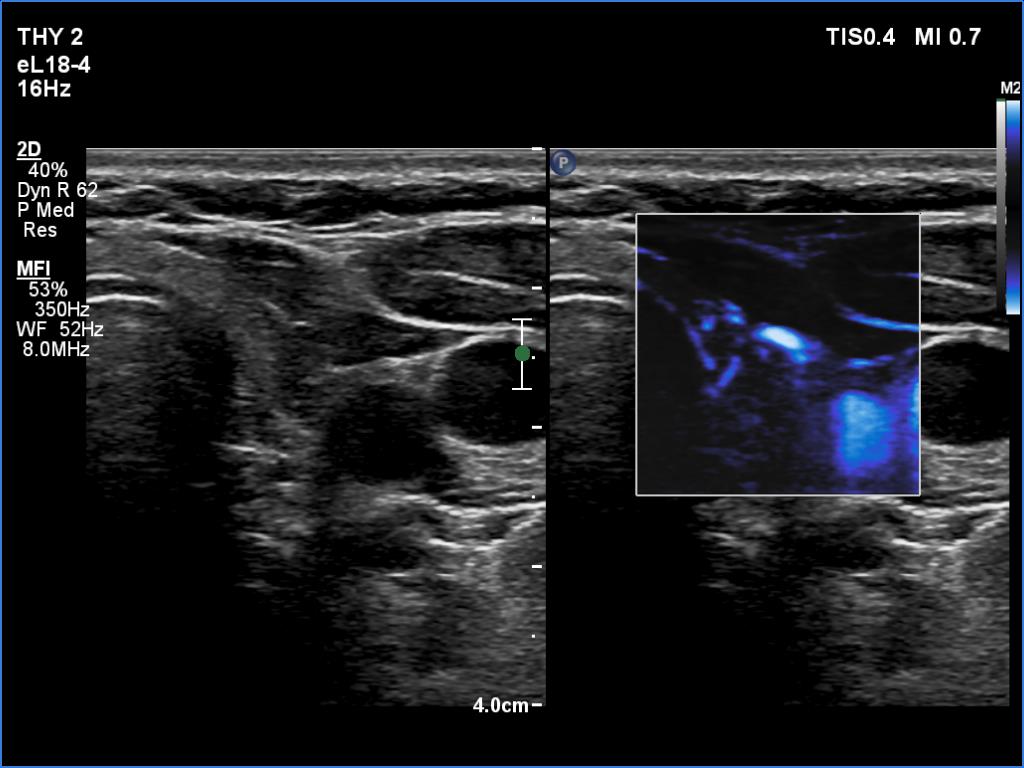

Follow-up examination five years later (ultrasonographic picture 8)

Left lobe, transverse scan, microflow imaging. The vascularity is decreased.